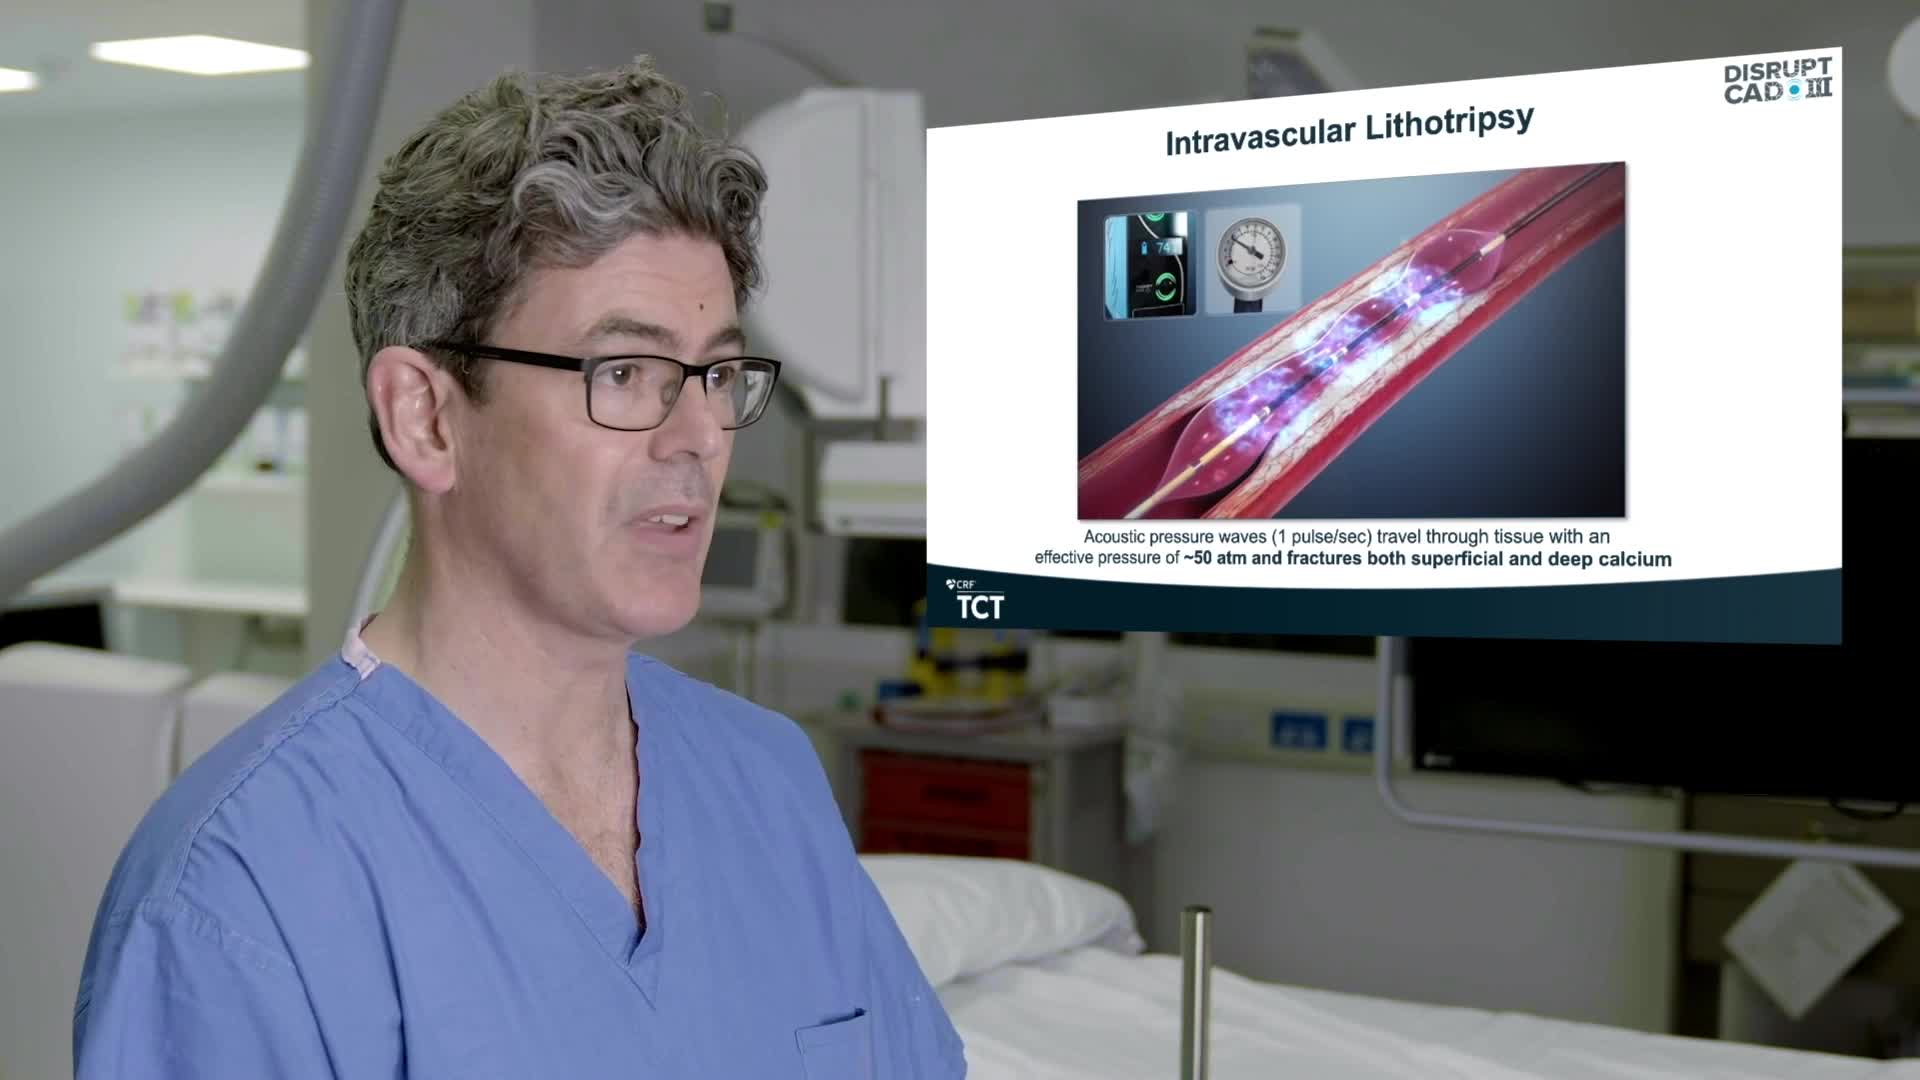

Simplify your procedures with Intravascular Lithotripsy (IVL) by safely modifying intimal and medial calcium to achieve optimal outcomes while minimising trauma, complications and costs due to its unique MOA.

Intravascular Lithotripsy for Treatment of Severely Calcified Coronary Artery Disease: The Disrupt CAD III Study